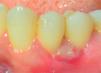

Clinical examination revealed an inflammatory gingival lesion at the level of teeth 3.4 and 3.5. Measuring approximately 15 x 9 mm. The lesion covered the vestibular side of the clinical crown, it was firm, lobulated, of rugged texture and bleeding upon stimulus (Figures 1and2). Periodontal assessment did not reveal periodontal pockets; presence of plaque was observed, and an O’Leary oral hygiene index of 18.75 was determined. Radiographic evaluation revealed absence of interproximal contact between teeth 3.4 and 3.5 as well as restorative material in the interproximal area (Figure 3).

Controls: lesion volume decreased after a week, nevertheless, the area still exhibited a reddish hue, therefore, it was kept under observation (Figure 7). Two weeks later, a slight volume increase with whitish and reddish hue was observed, thus a relapse was suspected. At the third week decrease of tissue volume was observed without any presence of inflammatory signs.

During a seven month follow-up suitable oral hygiene level was observed, no lesion relapse was observed (Figure 8).